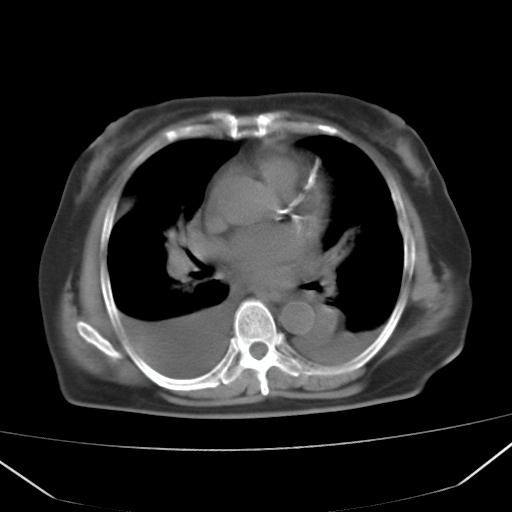

以下是引用liuyue在2008-4-19 22:25:00的发言:[br]先考虑:1.心衰伴肺水肿、双侧胸腔积液、叶间积液、双下肺不完全性肺不张; [br] 2.冠状动脉粥样硬化。

以下是引用lijuanln在2008-4-19 23:05:00的发言:[br]两侧胸腔积液,肺水肿[br]心包积液[br]提示心衰

以下是引用jiangjing在2008-4-20 10:43:00的发言:[br]结合病史支持 冠心病[冠状动脉钙化],心功能不全,肺淤血、肺水肿,双侧胸腔与斜裂积液